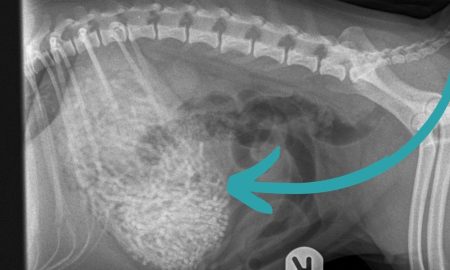

Indijac (26) je vjerovatno brzo požalio zbog svoje besmislene ideje. Kako bi brže došao u top formu, muškarac iz Delhija progutao je...